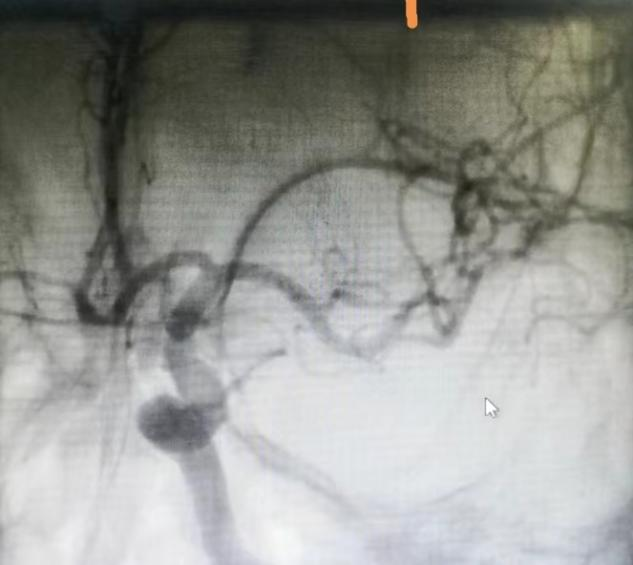

堵塞的左侧大脑中动脉

取栓后血管再通,血流恢复良好